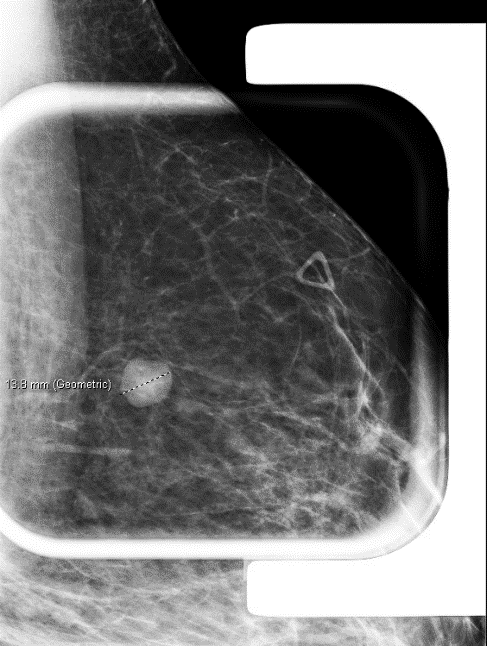

A 32-year-old female with a left breast suspicious mass at 12:00 o’clock underwent a needle biopsy.